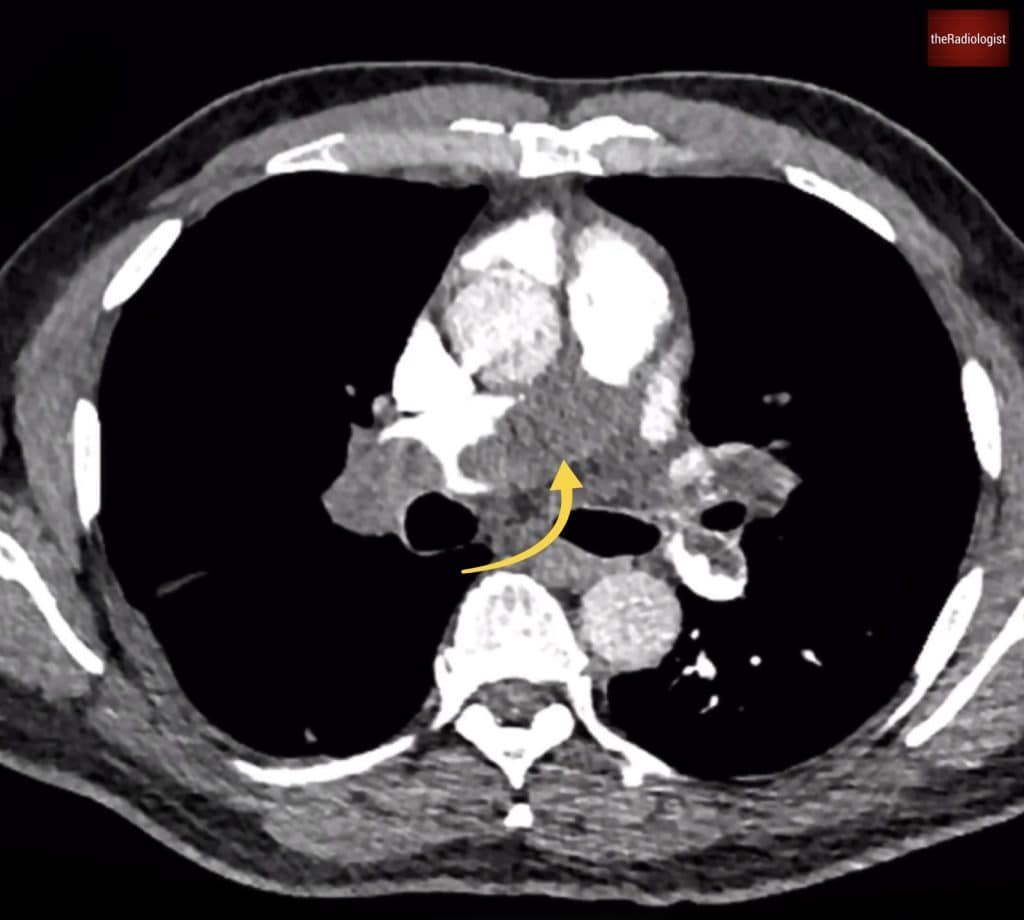

Now let’s look at the scan findings. If we follow the pulmonary arteries in this case, we’ll see that there are filling defects within the right main pulmonary artery. This extends into the right upper lobe pulmonary artery. This extends into all three right sided lobes, and we can see in some areas we have our polo sign, where we have a filling defect and contrast around this. Polo refers to the mint not the horse game (other mints are also available) and this sign suggests acute pulmonary emboli.

We can see in our case there are filling defects within the pulmonary arteries. On the left image there is a filling defect within the right main pulmonary artery (yellow arrow). Going into the right lower lobe on the right hand image we can see a ‘polo sign’ (white arrow) suggesting the pulmonary emboli are acute.